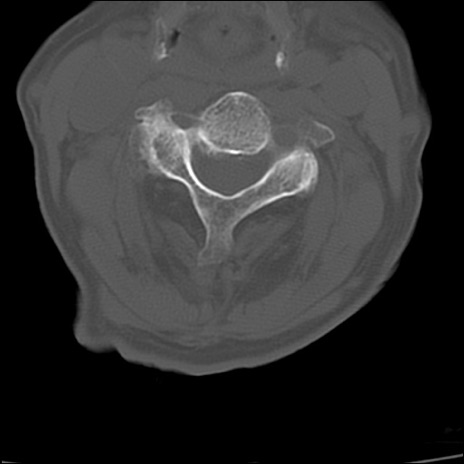

症例48 頚椎CT(横断像)

頚椎CT